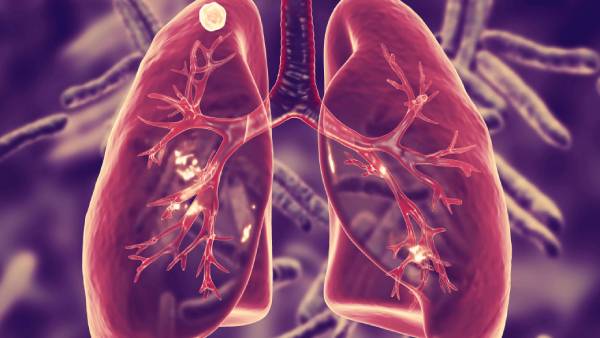

இந்தியாவின் முக்கிய சுகாதார சிக்கல்களில் ஒன்றாகப் பட்டியலிடப்பட்டுள்ள காசநோய் பாதிப்பால் ஆண்டுதோறும் சுமார் 4.80 லட்சம் இந்தியர்கள் உயிரிழக்கின்றனர். அதாவது சராசரியாக 1400 பேர் காசநோயால் பலியாகின்றனர். இது அதிகாரப்பூர்வ தகவல். இதுபோக பல லட்சம் பேருக்கு காசநோய் பாதிப்பு உறுதி செய்யப்படாமலேயே மிஸ் ஆகிவிடவும் வாய்ப்புள்ளதாக மருத்துவர்கள் எச்சரித்துள்ளனர்.